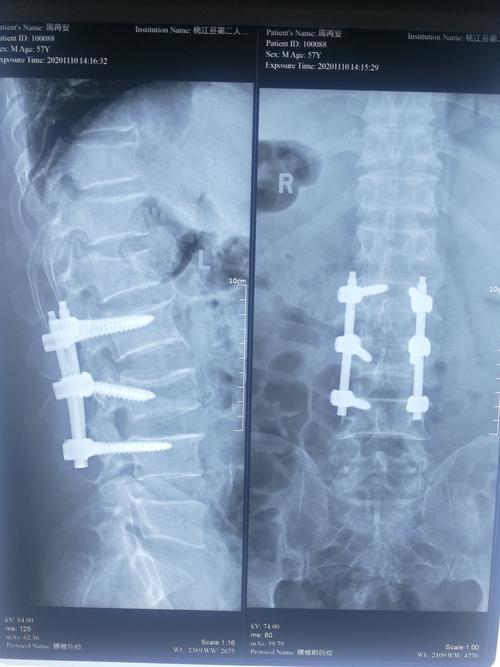

腰椎手术后下床活动的时间取决于手术类型和个体恢复情况微创手术一般制动一个星期以后便可以下地活动椎间盘摘除手术伴内固定和椎孔减压这种大手术后,需严格卧床休息两周左右,期间可以翻身但避免坐立多数建议在三周至四周后,部分负重并借助助行器下地活动腰椎压缩性骨折的微创骨水泥手术术后;腰椎骨折后下床的时间取决于治疗方法和患者的具体情况保守治疗一般需要卧床68周的时间在此期间,应睡硬板床,并适时进行腰背肌功能锻炼下床前需拍片子检查骨折愈合情况,确认无误后才可下床下床时需进行腰围固定,休息时取下手术治疗一般手术后23周可以在支具的保护下逐渐下床行走如果是单纯;下床时间术后第2天即可下地行走及进行活动功能锻炼原因该手术方式通常使用骨水泥固定椎体,使其非常稳定椎弓根钉内固定术下床时间术后1个月才能下地活动及进行功能锻炼原因该手术方式虽然进行了内固定,但椎体中间仍处于相对空虚的状态,需要等待4周后骨折达到临床愈合,下地才相对安全;腰椎骨折手术后可以下床的时间取决于具体的手术方式传统开刀手术方式术后一周左右采用传统开刀手术方式并进行内固定后,患者通常可以在术后一周左右,适当佩戴胸背部的支具下地行走微创椎体成形术术后三天左右如果采用的是微创椎体成形术,通常在伤后三天左右拔除引流管后,患者就可以适当下地。